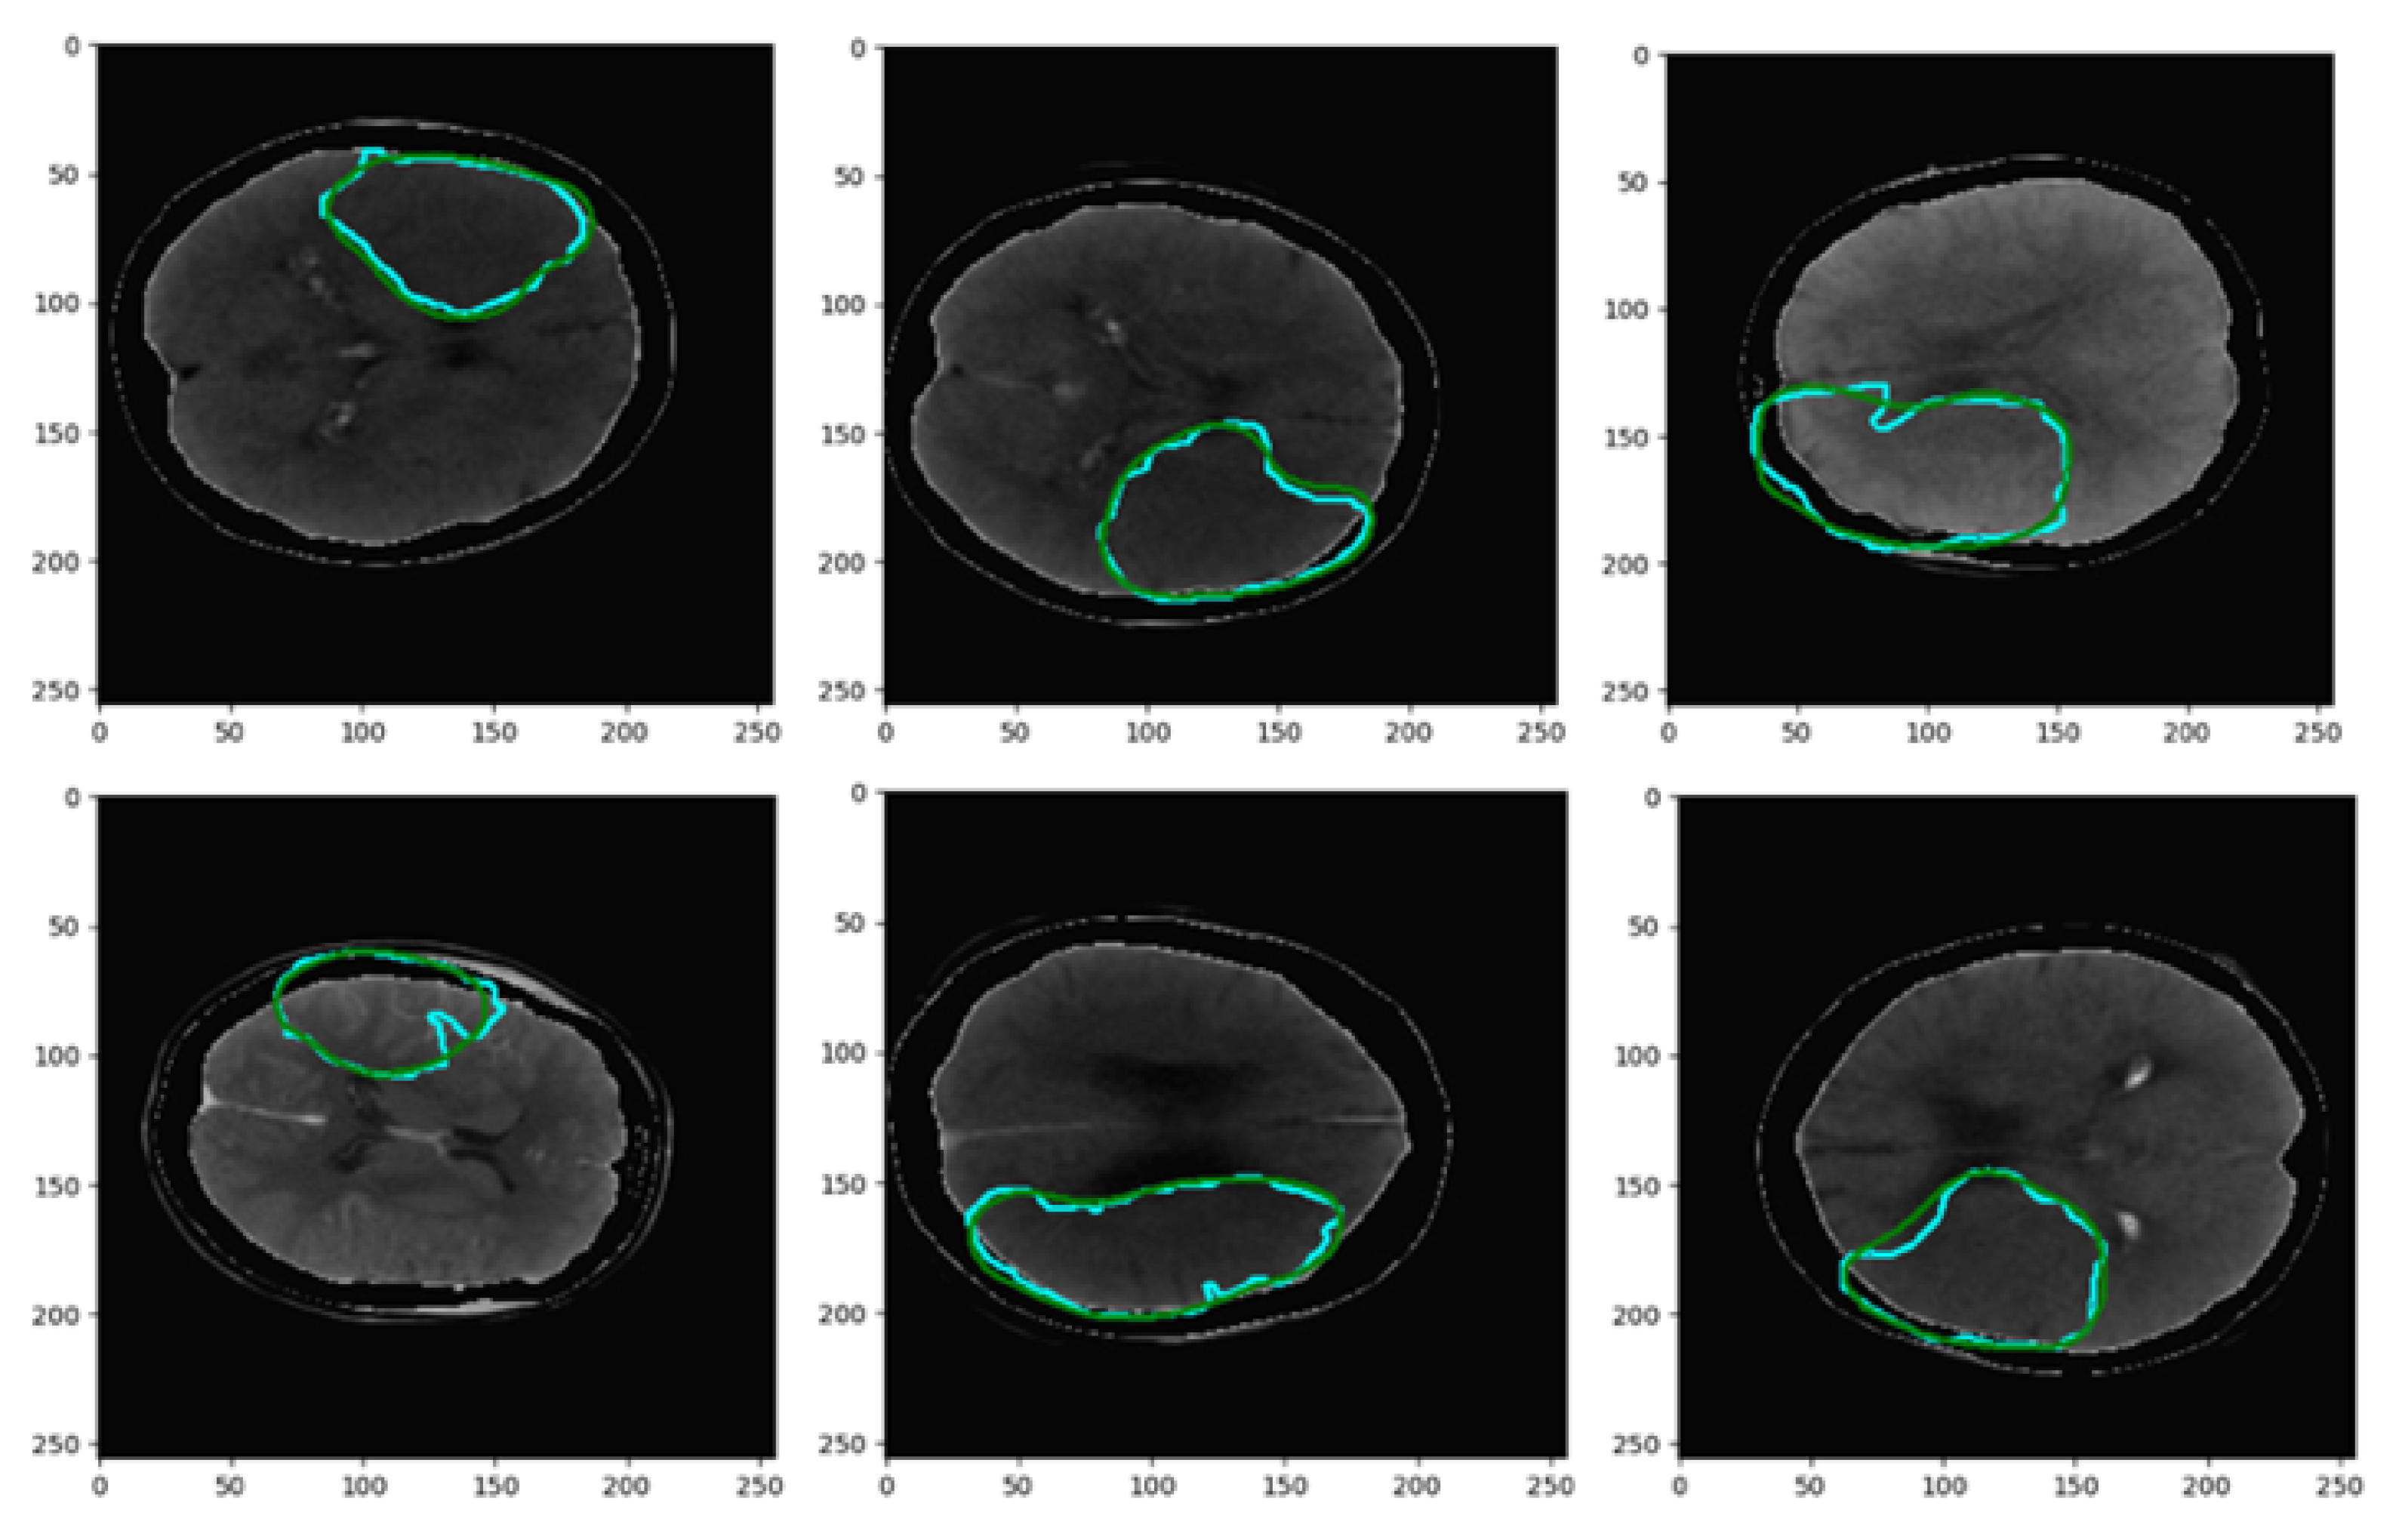

- The proposed network utilizes a channel of perfusion maps, including CBV, CBF, MTT, Tmax, and CT slice, to efficiently extract the stroke lesion.

3.1. Pre-Processing of Data